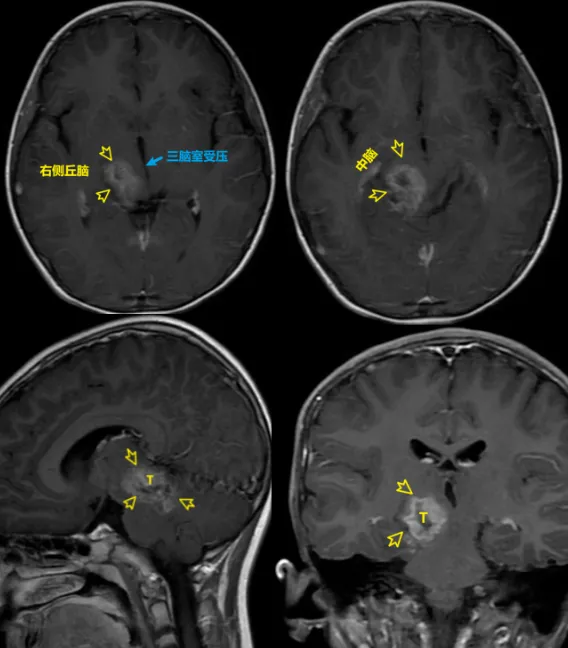

年仅7岁的珂珂因复视、呕吐而查出脑瘤,肿瘤已经累及脑干中脑、丘脑两大关键位置,导致三脑室受压。

儿童丘脑胶质瘤多为低级别(如毛细胞星形细胞瘤),但常沿白质纤维束浸润,与正常脑组织缺乏明确分界。影像学显示的“边界”常小于实际浸润范围。同时,肿瘤压迫中脑导水管后还会导致急性梗阻性脑积水,需优先处理脑积水,再择期处理肿瘤,增加了手术阶段的复杂性。